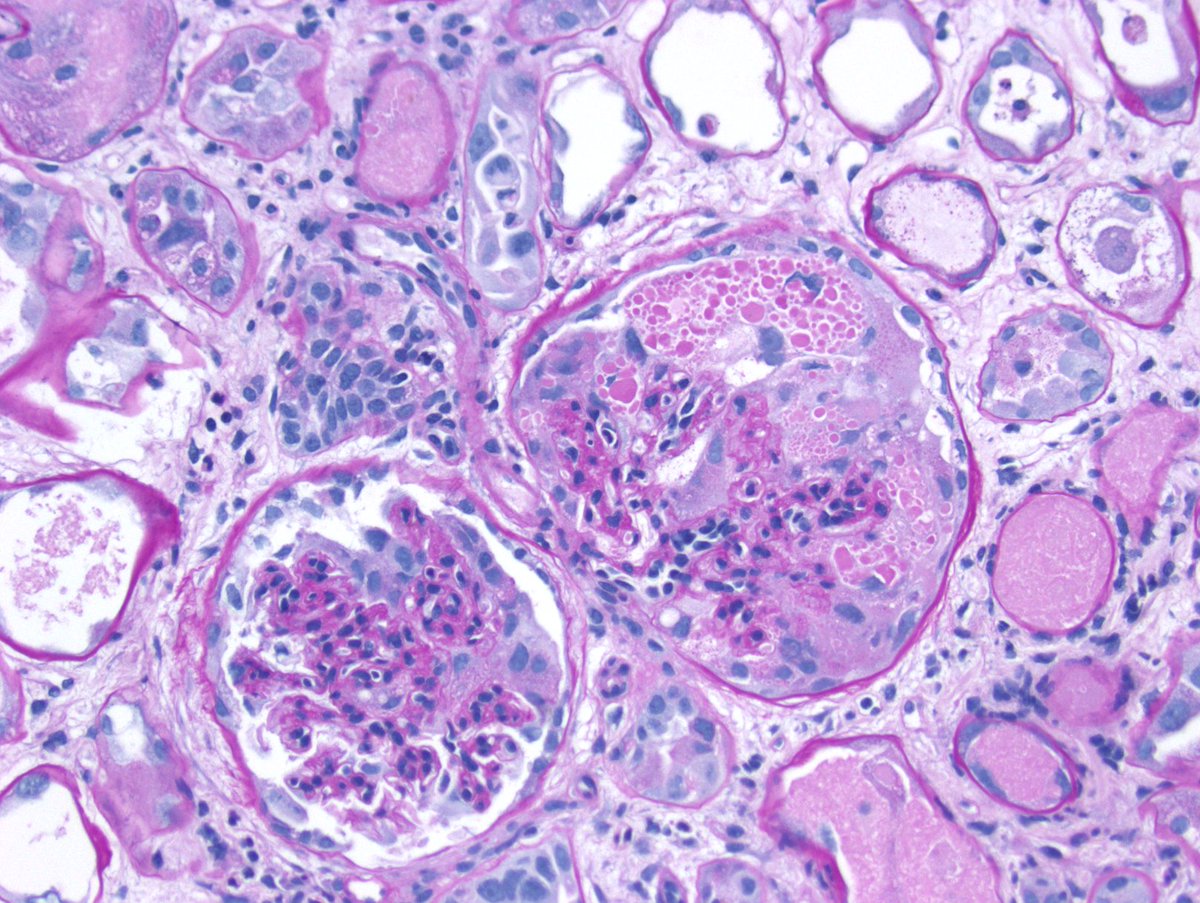

Long weekend often brings urgent cases. Here is one that was STATed, ended up showing anti-GBM GN. Diffuse crescents (nearly 100%). Linear IgG. #RenalPath